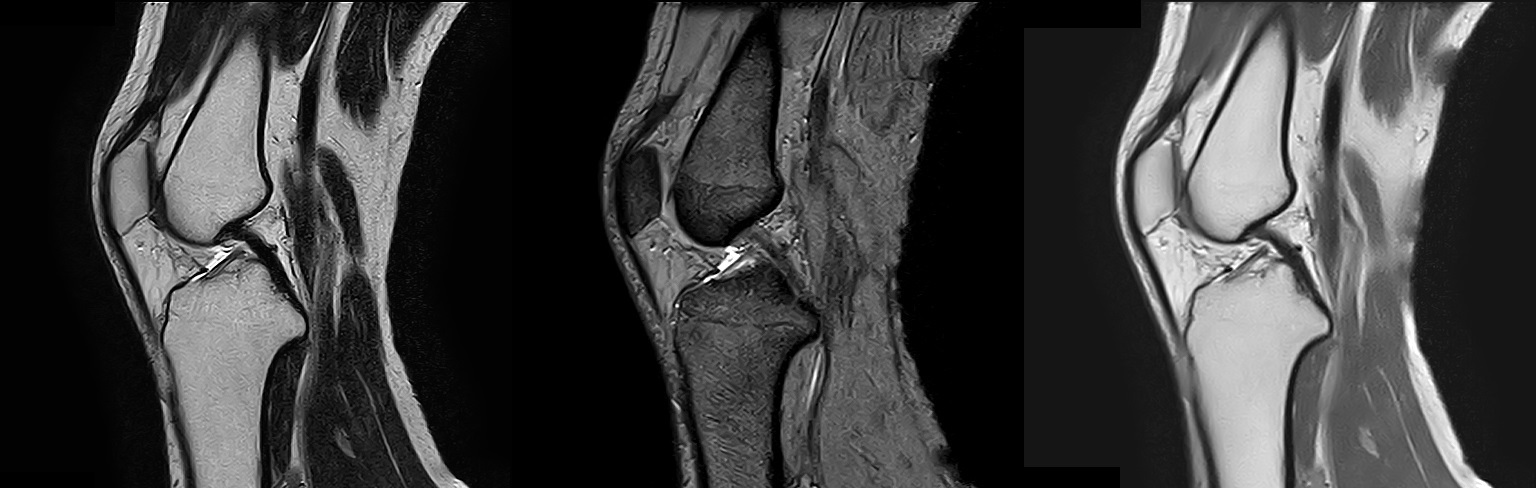

MRI(磁気共鳴画像)装置

2022年2月にMRI装置を更新いたしました。

1.5TのMIR装置(富士フイルムヘルスケア株式会社製「MRイメージング装置 ECHELON Smart」)を導入し、以前よりも短い時間で高画質の撮像が可能になりました。

MRIは体内の断面像を縦、横、ナナメから人体に悪影響を与えずに見ることが出来る装置です。わずかな病変も見逃さない鮮明な画像は腫瘍などの早期発見や健診に威力を発揮します。薬品を全く用いずに血管撮影等が出来るので、患者さんは動かずに横になるだけで苦 痛なく精密検査が受けられます。

MRA

T2強調像 / T2*強調像 / プロトン密度強調像